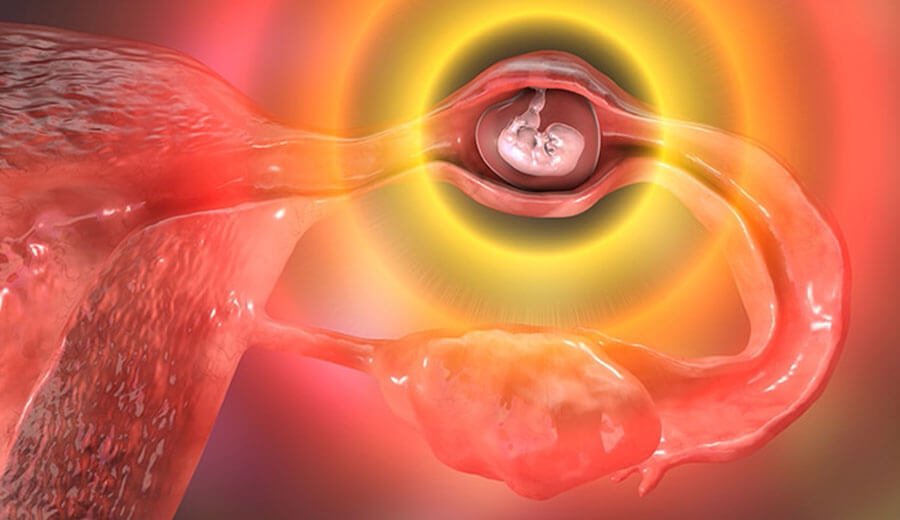

Cirurgia de gravidez ectópica

Procedimento cirúrgico no qual as trompas de falópio são bloqueadas para prevenir a gravidez. É uma opção segura e eficaz para mulheres que não desejam ter filhos no futuro.